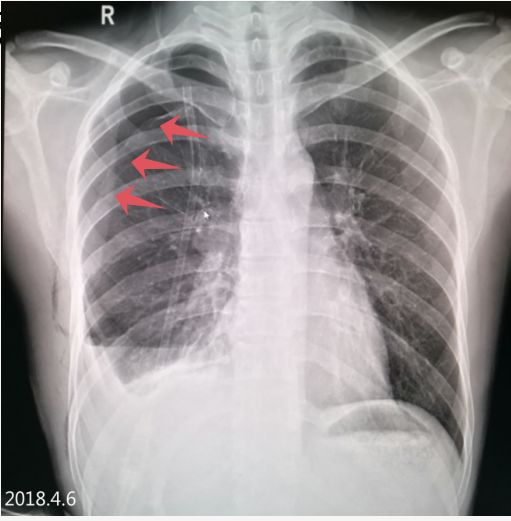

2018.4.6 气胸复张,右下肺见液平面